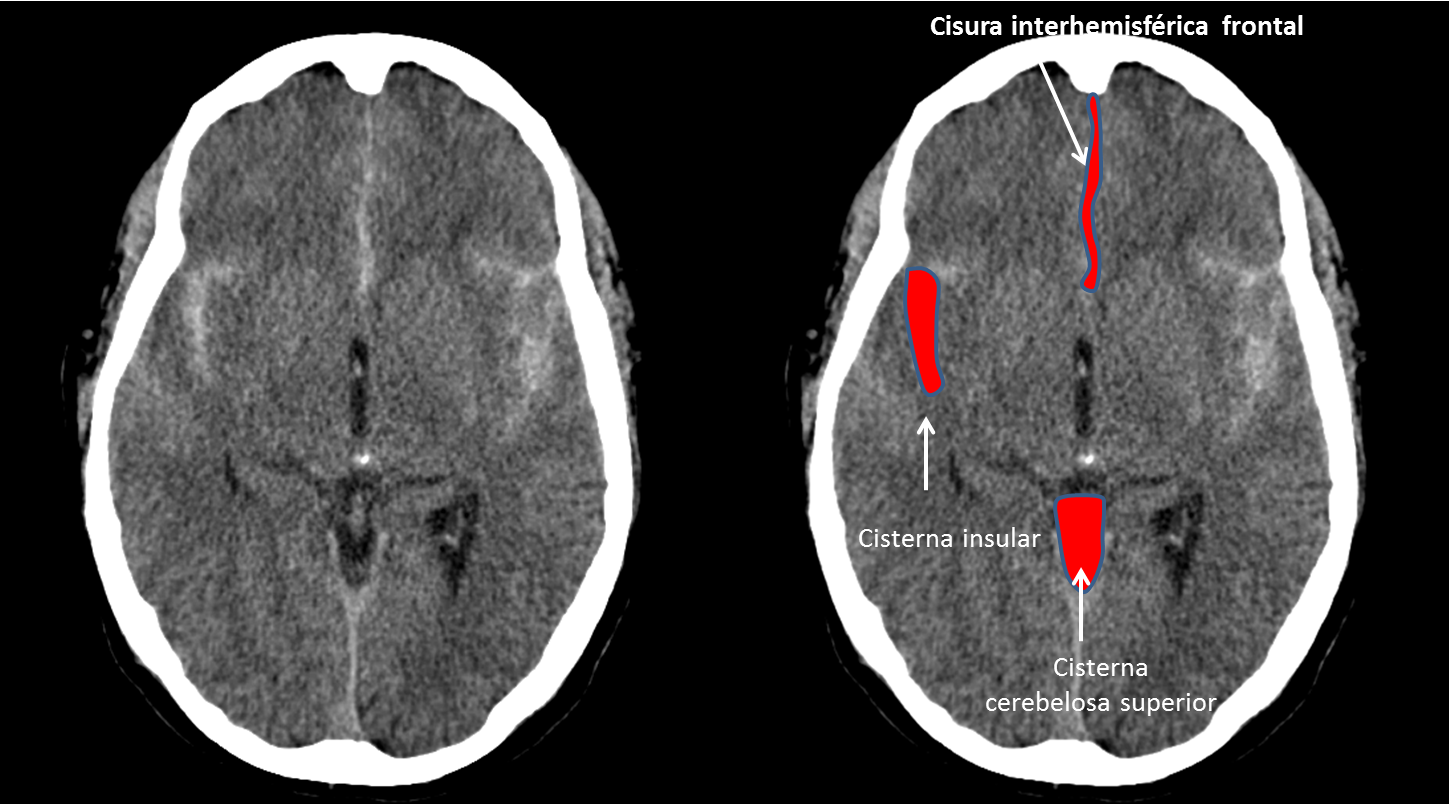

Continue reading →: Infarto cerebral talámico